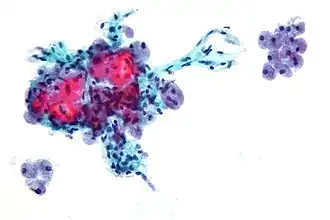

Клетки Гюртле (Hürthle cells) — это большие клетки, часто ассоциированные с фолликулярным раком щитовидной железы. При микроскопическом исследовании окрашенных культур имеют розовый цвет. Клетки названы в честь немецкого патолога Карла Гюртле (1860—1945)[1].